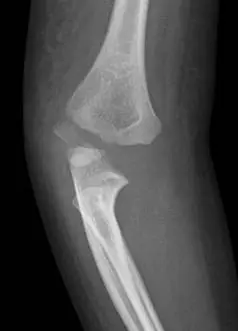

4歲小美由床上跌落,由於右肘的疼痛及腫脹,父母帶她來急診求診,並接受右肘部的 X光檢查,由此 X光影像,顯示此女童發生了何種骨折?

本題提供兩張右肘 X 光影像:

側面(Lateral)影像: 外髁骨折碎片向後外側移位,可見後脂肪墊徵象(posterior fat pad sign)陽性,提示關節內積血。前肱骨線(anterior humeral line)仍通過肱骨小頭中三分之一,排除典型的髁上骨折(supracondylar fracture)。肱橈線(radiocapitellar line)異常,進一步支持外髁骨折之診斷。

綜合影像判讀: 骨折碎片位於外側,累及肱骨小頭骨化中心,位移方向為外側及後側,屬於 Jakob 分類 Type III(移位 > 4